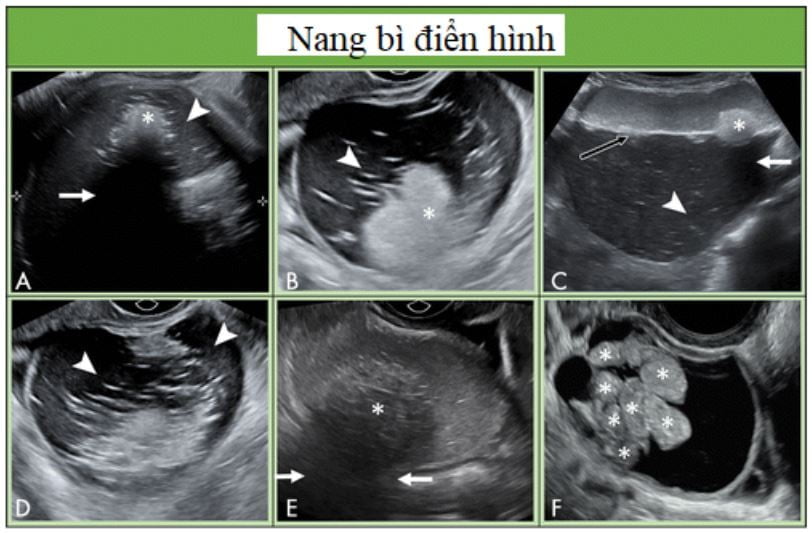

Hình 11: Hình cho thấy các nang bì điển hình. A, Nang bì với thành phần phản âm dày (dấu sao) với bóng lưng phía sau (mũi tên) và các đường và nốt tăng âm (đầu mũi tên). B, Các đường, nốt và thành phần tăng âm ở nang bì khác. C, siêu âm ngã bụng của nang bì cho thấy mức dịch dịch (mũi tên đen) với thành phần mỡ trôi nổi bên trong. Thành phần tăng âm (dấu sao) cho bóng lưng (mũi tên) và những đường tăng âm nhẹ và các đốm (đầu mũi tên) cũng thấy được. D, Sang thương dạng nang với chủ yếu là các đường và chấm tăng âm (đầu mũi tên), tương ứng với thành phần tóc trong nang bì. E, Thành phần tăng âm (dấu sao) với bóng lưng (mũi tên) trong nang bì có hồi âm bên trong. F, Những cấu trúc hình cầu trôi phản âm (dấu sao) không thường gặp nhưng là điểm đặc trưng bệnh học của nang bì.